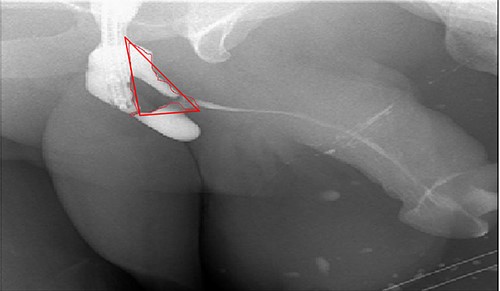

A 38-year-old male was referred to our tertiary hospital due to recurrent urethral stricture for further evaluation and management. His history revealed multiple failed attempts of DVIU, anastomotic urethroplasty and urethroplasty with pedicled fasciocutaneous flap in 2019. Nine months after his surgery, he had complete retention due to stricture recurrence and he underwent multiple dilatations and DVIU but his stricture keep recurring. He was referred to us for definitive management. He was on a suprapubic catheter. Initial workup included retrograde, antegrade cystoscopy and urethrogram. First, an antegrade cystoscope was introduced. The bladder neck, internal sphincter and verumontanum were identified. However, there was no external sphincter due to damage from the previous procedures. A pinpoint opening in the dorsal area of the urethra was seen about 1-cm distal to the verumontanum (Fig. 1, lumen A). Also, a blind-ended urethra in the ventral area was identified (Fig. 2, lumen B). It is most likely from the previous flap. Additionally, the retrograde urethrogram showed that the contrast was only going from the pinpoint hole in the dorsal side of the urethra Fig. 3. Retrograde cystoscopy also showed a blind-ended in the proximal bulbar urethra. We could not identify the small hole that we saw from the antegrade cystoscopy. After initial workup, he was counseled in the clinic for dorsal only buccal mucosal graft (BMG) urethroplasty for which he agreed.

(lumen B): A blind-ended urethra in the ventral area of the urethra as pointed in the arrow.